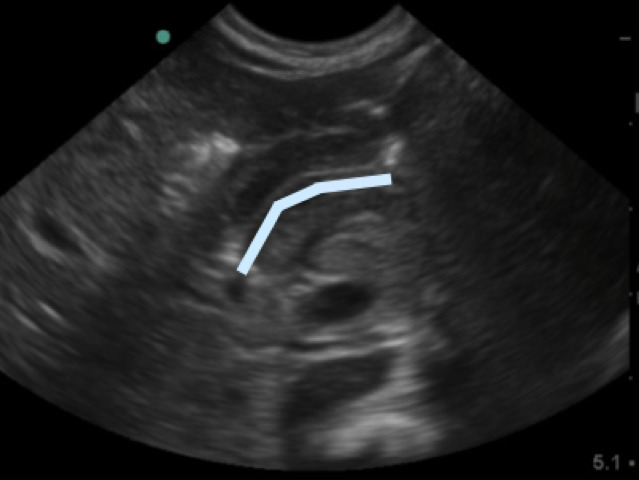

- Figure 4a. Long axis view of the pyloric musle (M) highlighted by white arrows at the distal end of the stomach (St)

- In between the pyloric muscles is the hyperechoic pyloric channel made up of gastric mucosa.

- Figure 4b.Highlighted pyloric channel made up of gastric mucosa